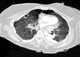

Lung torsion